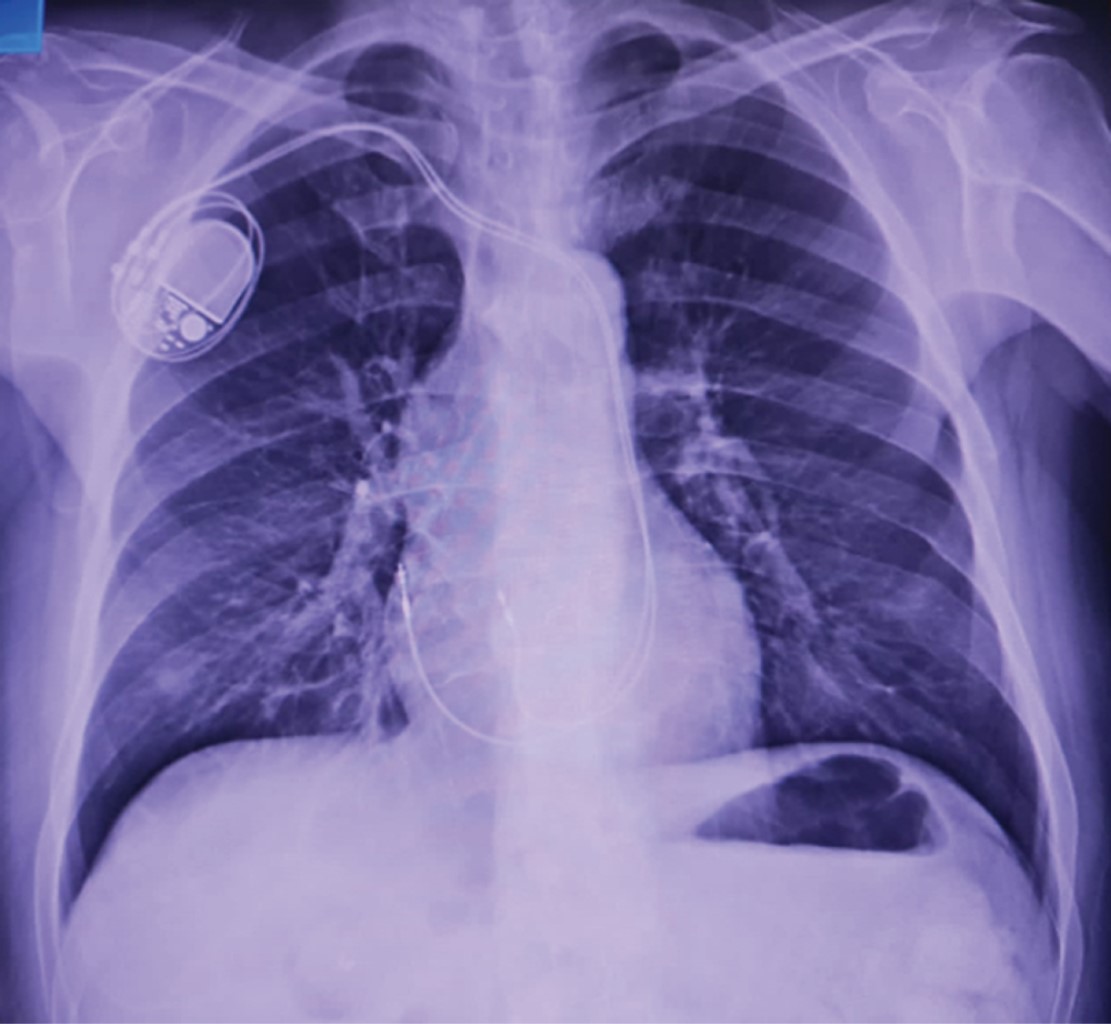

Pacemaker implantation through the persistent left superior vena cava due to the absence of the right superior vena cava. Report of a case

Introduction: the persistence of the left superior vena cava (PLSVC) has a prevalence of 0.21% in the general population. Case presentation: 67-year-old male diagnosed with third-degree AV block, requiring pacemaker placement. However, due to the absence of a right superior vena cava, corroborated by CT angiography, a definitive pacemaker was placed through a persistent left superior vena cava. Conclusion: the persistence of the left superior vena cava (PLSVC) is the most common thoracic venous anomaly. It can cause a number of clinically significant symptoms, even in a heart with normal anatomy. Pacemaker placement makes electrode fixation difficult due to tortuous travel.

Figure 2